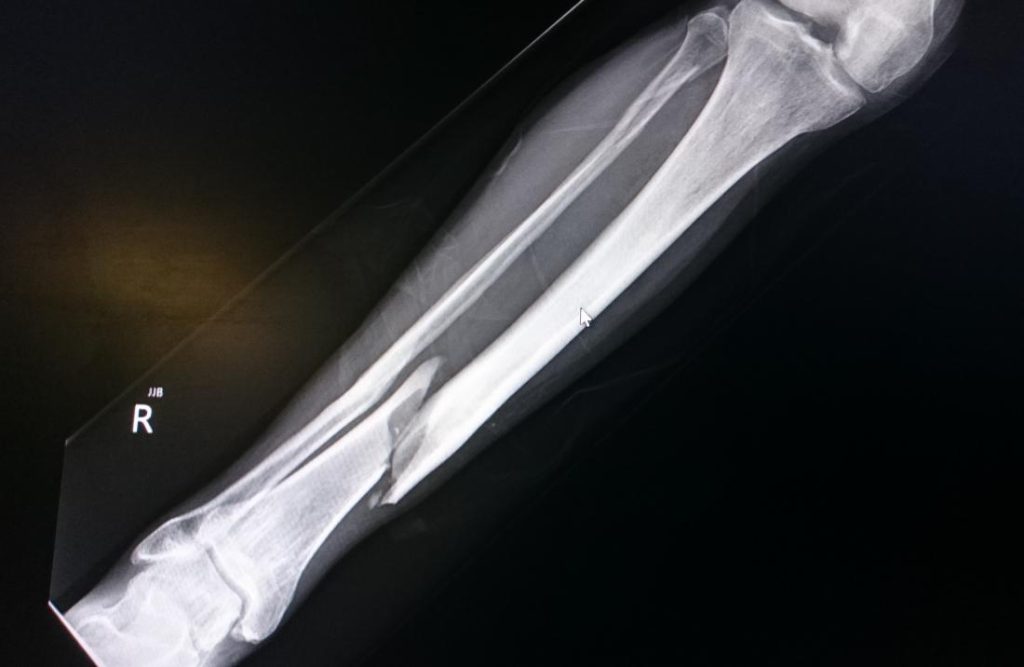

A spiral fracture is a specific kind of bone fracture that occurs via a twisting movement on a bone and leaves a fracture line that resembles a corkscrew. Spiral fractures often affect long bones in the human body. Among the most prevalent are:

- Tibia

- Fibula